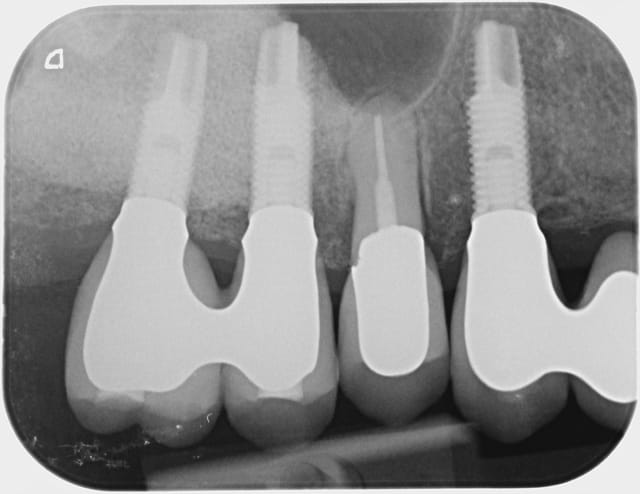

Les 2 premières radios datent de 2009, la dernière d'hier.

L'occlusion est bonne, douleurs modérées à la pression et mobilité type 1-2.

Quelle est la cause de cette migration selon-vous?